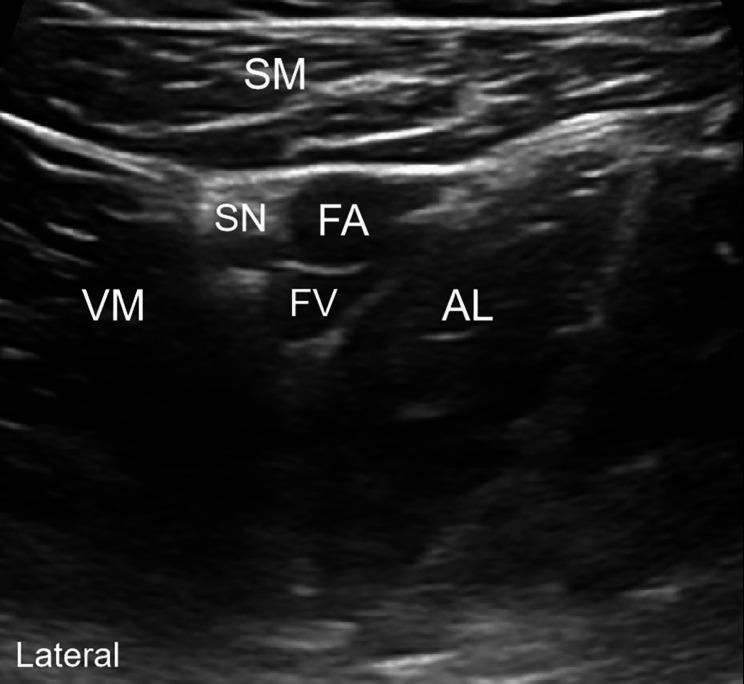

This randomized controlled and double-blind study aimed to investigate whether the analgesic effect of the adductor canal block (ACB) combined with the genicular nerve block (GNB) after total knee arthroplasty is noninferior to that of the adductor canal block combined with local infiltration analgesia (LIA).

A total of 102 patients undergoing total knee arthroplasty under general anesthesia were included and randomly divided into: ACB + GNB and ACB + LIA groups; the ACB + LIA group received 80 mL of 0.2% ropivacaine with adrenaline 10 µg/mL for LIA, whereas the ACB + GNB group received 4 mL of 0.2% ropivacaine for the blockade of five peri-knee nerves. The primary outcome was the median difference in the visual analog scale scores at rest at 24 h between the two groups. Secondary outcomes involved the median differences in the pain scores at other time points. Other outcomes included the cumulative dosage of opioids calculated in morphine equivalents in the first 24 h and indicators related to knee joint functional recovery.